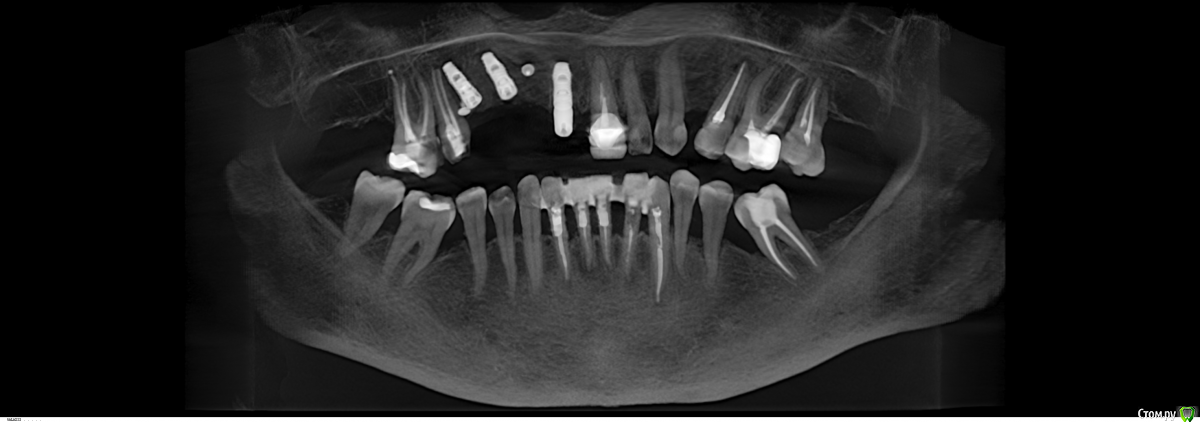

Robinbobin Опубликовано 9 сентября, 2015 Поделиться Опубликовано 9 сентября, 2015 Зуб 1.1 удалил,кюретаж и одномоментно установлен имплантат, заполнил MP3 и закрутил заглушкуУстановил имплантаты в области 1.3,1.4 подсыпал так же MP3 под мембрану и запинилЕсли покажите пальцем на ошибки буду благодарен))) 4 Ссылка на комментарий

Большой Зеленый Опубликовано 9 сентября, 2015 Поделиться Опубликовано 9 сентября, 2015 11 имплант нужно было медиальнее ставить и чуть еще утопить платформу 1 Ссылка на комментарий

Bier Опубликовано 13 сентября, 2015 Поделиться Опубликовано 13 сентября, 2015 ставить нужно учитывая шейку будущего зуба, а не глубже "потому что часть кости уйдет" Тут будет некрасивая ортопедия. 2 Ссылка на комментарий

SergeyAL Опубликовано 13 сентября, 2015 Поделиться Опубликовано 13 сентября, 2015 полностью согласен, у ортопеда будет много проблем с эстетикой из-за разного уровня шеек имплантатов. Ссылка на комментарий